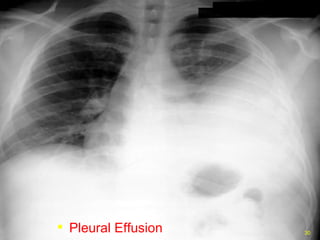

PLEURAL EFFUSION

Bilateral pleural effusions

• #29 Pleural effusion developing on the left